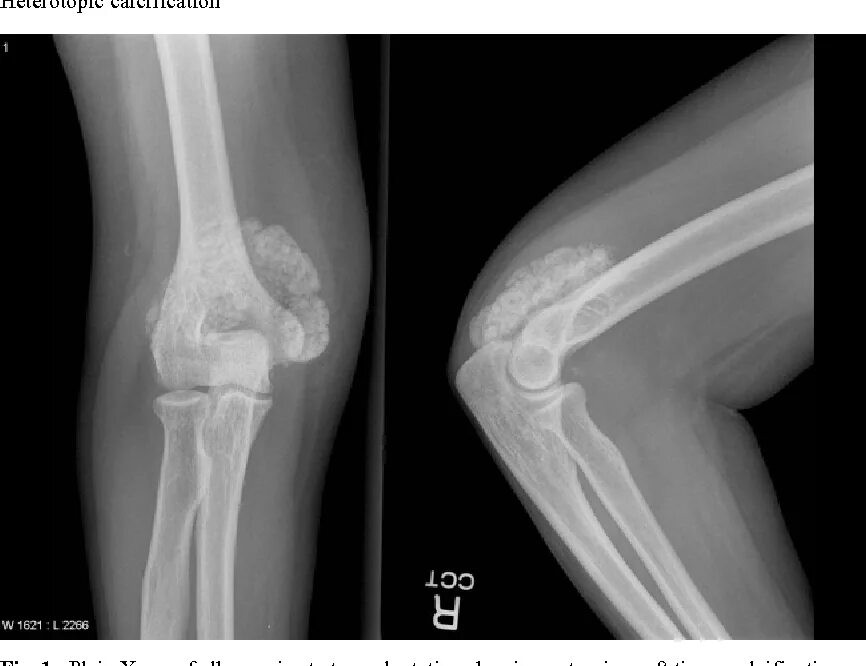

Обызвествление сухожилий мышц